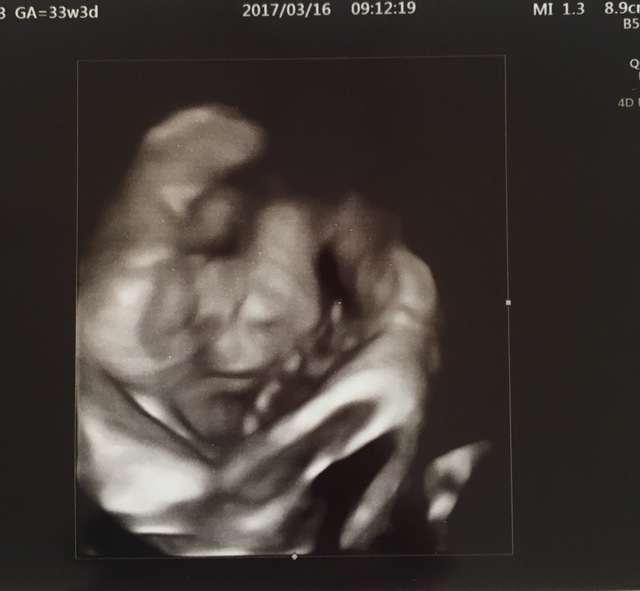

33週6日(33w6d・女の子)|しょーちゃん129 さん(27歳)

エコー写真撮影時のエピソード:

お顔がはっきり見えていることです!里帰り先の産婦人科では、4Dのエコー写真を毎回撮ってもらえる婦人科で、初めて4Dのエコー写真を見せて貰ったときの一枚です。普通のエコー写真ではわからない表情まで確認でき、こんなにしっかり育っているんだなーと感動しました!